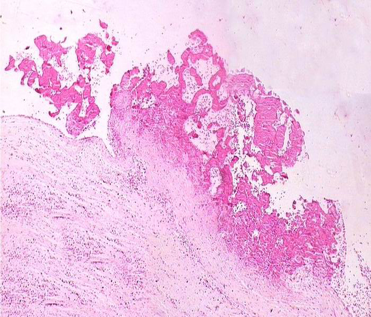

此期特点是在变质渗出的病变基础上形成具有特征性的病变,称之为风湿小体或阿少夫小体(Aschoff body),又称风湿小结或风湿性肉芽种(见下图)。

此种小体对诊断风湿病有意义。风湿小体的形成是在纤维素样坏死物质周边围绕数量不等的风湿细胞,它们是由增生的巨噬细胞吞噬纤维素样坏死物质转变而来,风湿细胞也称阿少夫细胞(Aschoff cell),有的文献称其为Anitschkow细胞。

风湿细胞体积较大,圆形、卵圆形,胞浆丰富,略嗜碱性,核大圆形或卵圆形,核膜清晰,核染色质集中于中央,横切面呈枭眼状,纵切面呈毛虫状。也可见多个核的Aschoff巨细胞。纤维素样坏死、成团的风湿细胞及伴有的淋巴细胞、浆细胞等共同组成的具有特征性的病变为风湿小体或阿少夫小体(Aschoff baody)。

(图3-1)